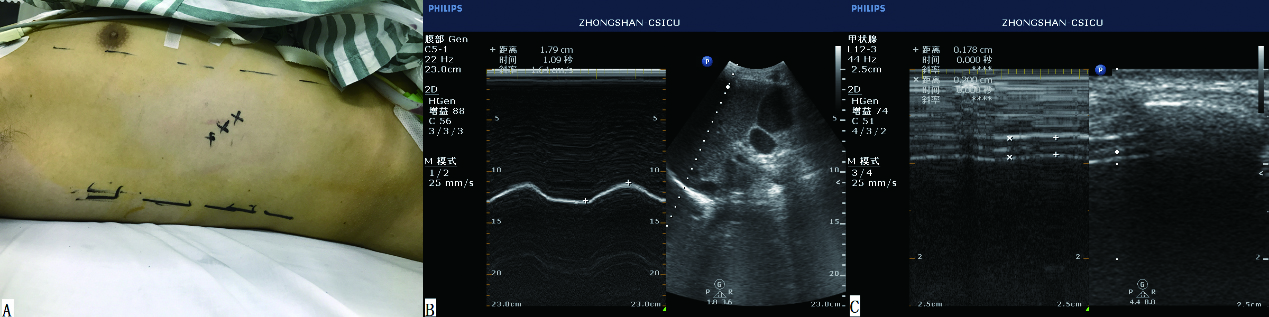

超声机器型号为飞利浦CX50,由有超声资质的同一位监护室医生测量。测量方法为:腹部探头测量双侧膈肌活动度,再通过血管探头测量双侧膈肌厚度,并计算膈肌厚度随呼吸运动发生的变异率。膈肌厚度变异率=(吸气末厚度-呼气末厚度)/呼气末厚度。具体方法为首先应用2D模式在腋前线或腋中线找到最佳测量路径(探头位置见图 1),然后选择M超测量膈肌位移或厚度。膈肌功能不全的定义为一侧膈肌活动度小于10 mm,或呈负向运动。负向运动指反常呼吸运动。

图 1 膈肌位移及厚度测量: A:超声探头置于左侧或右侧腋中线,两肋骨中间;B、C:M超显示膈肌位移及厚度 Figure 1 Measurement of diaphragm excursion and thickness:A: The probe was placed on the lower intercostal spaces of the midaxillary line. B and C: M model revealed the excursion and thickness of the diaphragm